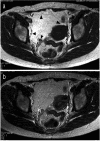

Retroperitoneal benign lipomas are extremely rare and represent about 2.9% of all primary retroperitoneal tumors. About 80% of the tumors in the retroperitoneal cavities are malignant neoplasms. We experienced a case of a retroperitoneal lipoma simulating an ovarian mature cystic teratoma. A diagnosis was correctly made by magnetic resonance imaging (MRI) prior to surgery, and a total tumorectomy was performed. The retroperitoneal lipoma was recognized to have arisen from the urinary bladder. Histological sections revealed a tumor consisting of typical adipose cells without atypia. These types of lipomas should be carefully followed-up because they often recur and undergo malignant transformations.